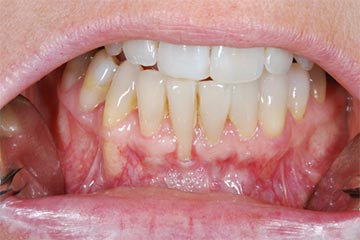

Con protesi fissa superiore e protesi fissa inferiore

sono stati sostituiti da 10 impianti, cioè protesi radicolari endo-ossee che sostengono le protesi fisse superiore ed inferiore.